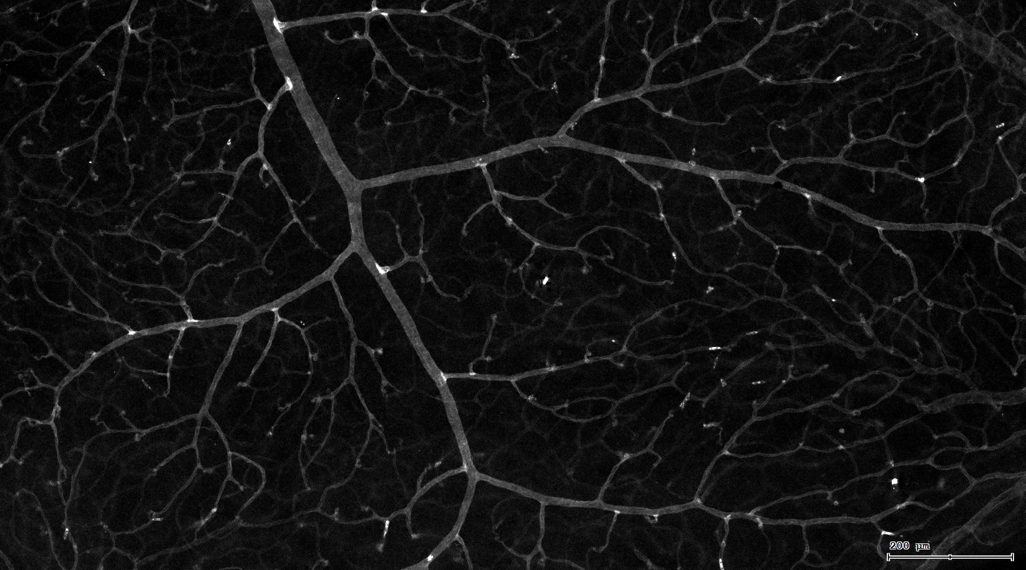

4. 膜识别FITC染色信号的区域确定神经纤维,并对不同长度神经纤维进行分类。

5. 识别血管的Texa Red染色区域面积及强度。

6. 计算神经元与血管间的空间距离,并统计数量和占比。

7. 根据毛细血管亮斑的识别结果,统计新生小血管数量。

血管识别:根据Texa Red通道进行识别,并去除面积小的及非同一焦面的血管,仅对确定的清晰的同一焦面的大血管进行面积统计。